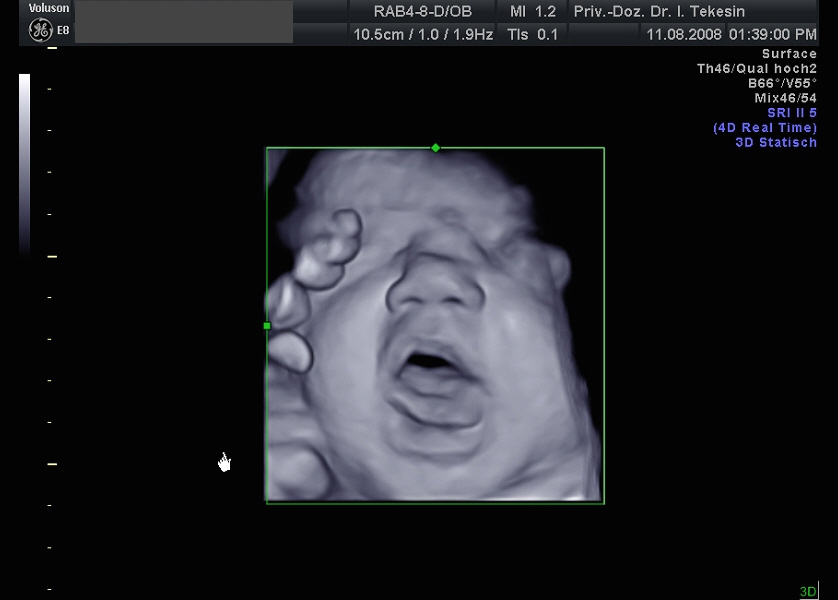

3D-/4D-Ultraschall (optional)

Immer mehr werdende Eltern interessieren sich für die faszinierenden Bilder, die dieses Verfahren liefert. Die plastische, dreidimensionale Darstellung der Oberfläche des Gesichts und anderer Körperregionen wird durch spezielle Bildrekonstruktion in schnellen Rechnern erreicht. Auch einzelne innere Organe oder „Gefäßbäume“ können von allen Seiten betrachtet werden. Viele dünne Schnittebenen (2D) werden zu einer gemeinsamen 3D-Sichtweise im Computer des Ultraschallgerätes zusammengeführt. Unter einem 4D-Ultraschall versteht man darüber hinaus eine 3D-Ultraschalluntersuchung unter Echtzeitbedingungen. Anstatt nur statische Bilder anzuzeigen, erfasst ein 4D-Ultraschall die Bewegungen des Kindes, weshalb er auch als „Live-3D-Ultraschall“ bezeichnet wird.

Diese Vorgehensweise ermöglicht äußerst realistische Bilder, bei denen sogar Gestik und Mimik des Kindes in bewegten Sequenzen festgehalten werden können. Die Untersuchung kann wie auch der normale Ultraschall während des gesamten Schwangerschaftszeitraums durchgeführt werden. Möchte man das Ungeborene komplett sehen, wird die 12. bis 16. Schwangerschaftswoche empfohlen, die Zeit zwischen der 28. und 33. Schwangerschaftswoche eignet sich besonders zur präzisen Darstellung einzelner Körperteile

Wir sehen in diesem modernen Verfahren in erster Linie eine ergänzende Maßnahme bei speziellen Fragestellungen bezüglich Herz, Gehirn oder Skelett und vor allem bei Verdacht auf eine fetale Besonderheit.

Ein gähnendes Kind in der 38. Woche

Ein freches Kind in der 38. Woche (3D-Darstellung)